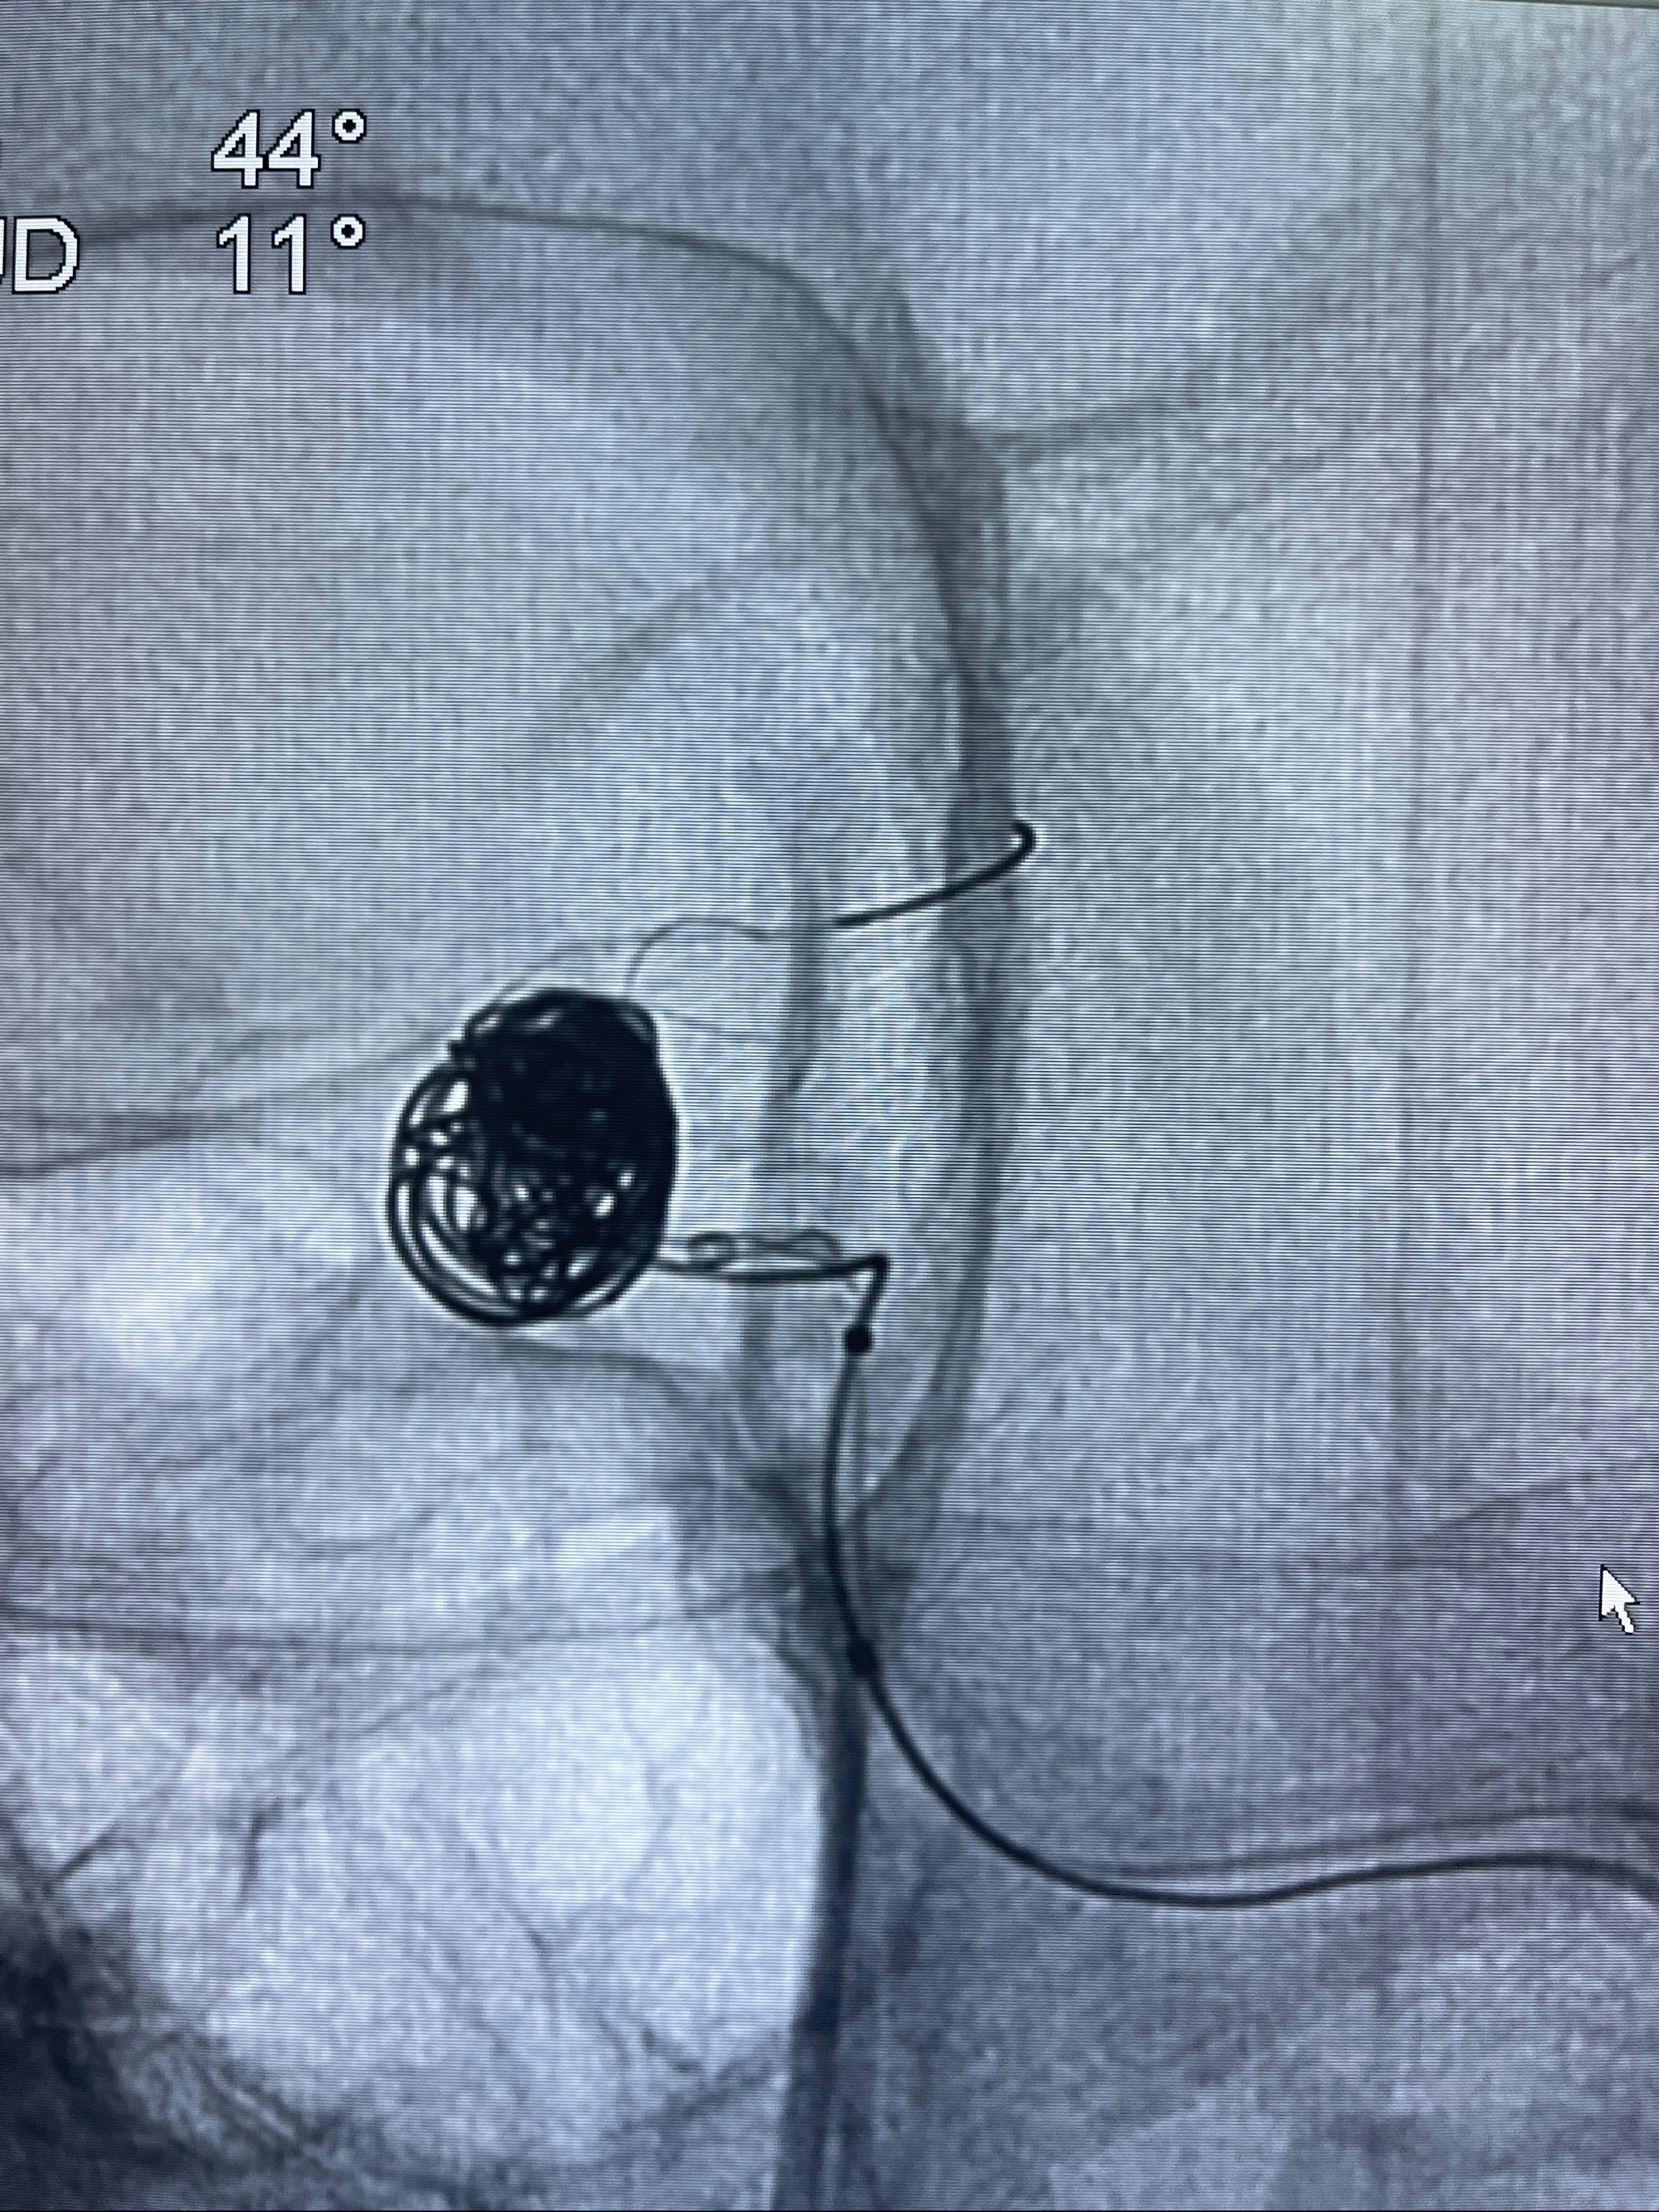

- Tubridge 4.0-20mm密网支架

- 加奇微弹簧圈:7*30/6*20/5*20/2*8

术后3D显示支架贴壁佳